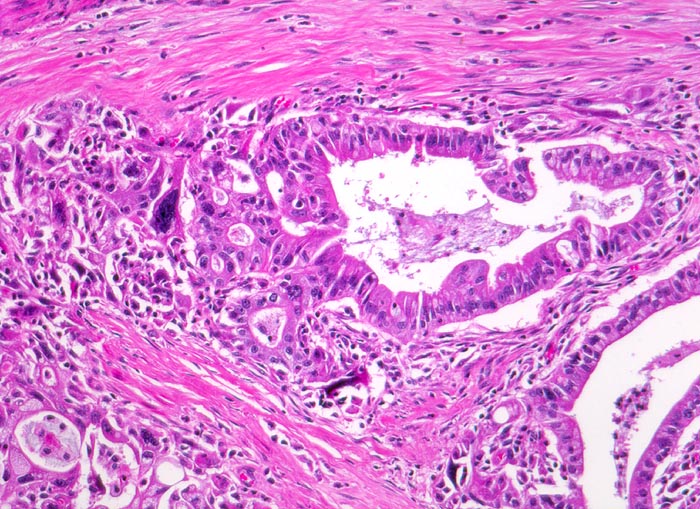

Die meisten Pankreaskarzinome sind mässig bis hoch differenziert und führen zu einer deutlichen desmoplastischen Stromareaktion (derbe Konsistenz). Hochdifferenzierte Tumoren (> 1502) können sehr ähnlich aussehen wie eine chronische Pankreatitis (> 4243). Im Gegensatz zur Pankreatitis sind die neoplastischen Drüsen verformt oder rupturiert und zeigen zelluläre Atypien (grosse polymorphe Kerne mit prominenten Nucleolen). Die Tumordrüsen sind unregelmässig im Stroma angeordnet und nicht lobulär wie in der Pankreatitis. Nicht selten ist eine Nervenscheideninvasion nachweisbar (> 5884). Gelegentlich zeigen die Gänge im tumorfreien Parenchym dysplastische Veränderungen oder der Tumor breitet sich intraduktal entlang des Pankreasganges aus.

• Kribriforme Drüsenformationen.

• Inkomplette Drüsen mit unvollständigen Lumina und Infiltration des Stromas durch Tumoreinzelzellen.

• Nekrotische Tumorzellen in den Drüsenlumina.

• Ausgeprägte Polymorphie und Hyperchromasie der Tumorzellkerne.

• Desmoplastisches Stroma.